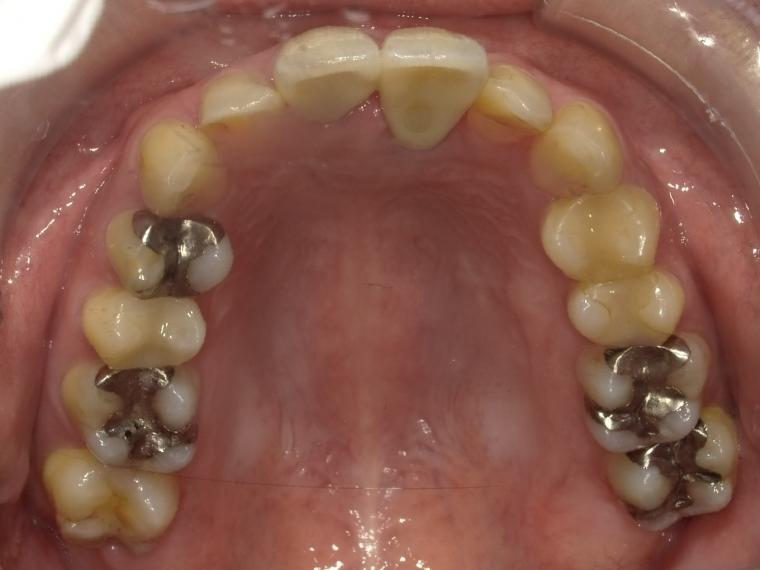

BEFORE

37歳女性/上1本欠損/インプラント埋込手術

左上前歯が脱臼した状態でご来院した患者さんです。

抜歯後に土台となる骨を作る処置の後、インプラントを1本埋入しました。